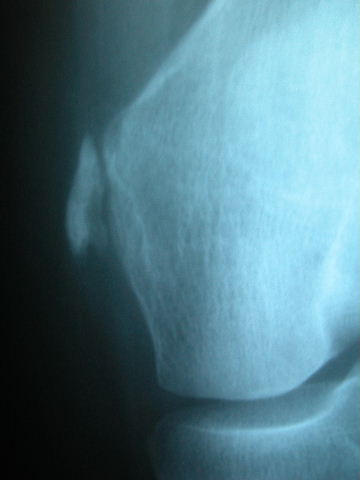

Prótesis completa de rodilla. Situación postquirúrgica.

Prótesis completa de rodilla. Situación postquirúrgica. Lateral.

Prótesis completa de rodilla.Lateral.

Prótesis completa de rodilla. Frontal.